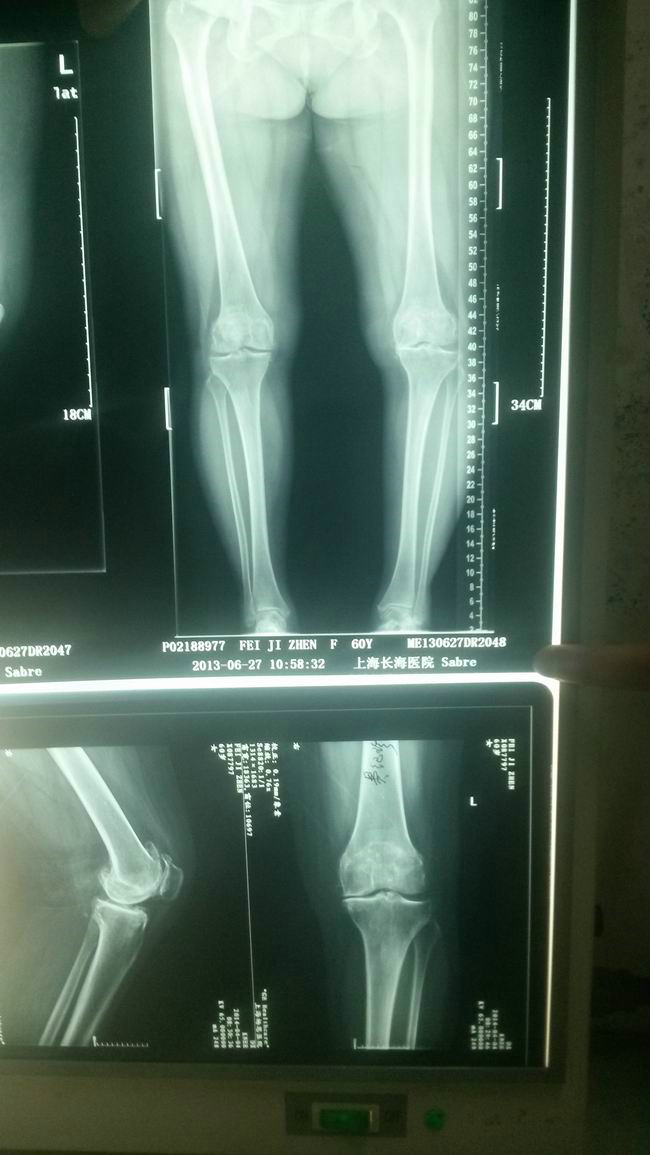

右膝关节治疗前、后X片对照